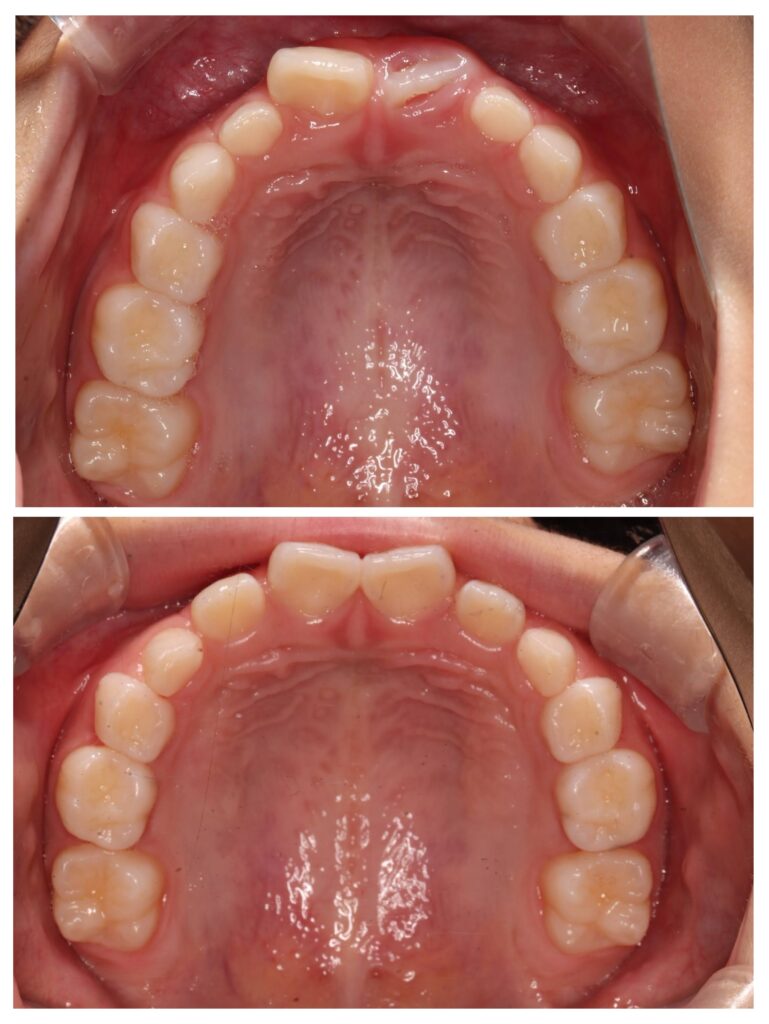

症例紹介①(顎顔面矯正)

今回の症例では、

成長期に上顎の拡大装置を使用。

BEFORE

歯列が狭く、前歯のスペース不足が認められました。

AFTER

歯列はU字型へ拡大。

永久歯が並ぶ余裕のあるアーチへ改善しました。